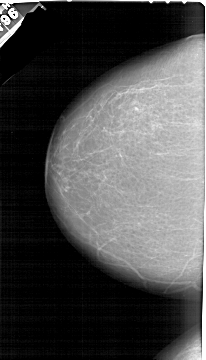

A_1255_1.LEFT_MLO

A_1255_1.LEFT_CC

LEFT_CC LINES 6466 PIXELS_PER_LINE 3691 BITS_PER_PIXEL 12 RESOLUTION 43.5 NON_OVERLAY

LEFT_MLO LINES 6421 PIXELS_PER_LINE 3736 BITS_PER_PIXEL 12 RESOLUTION 43.5 NON_OVERLAY